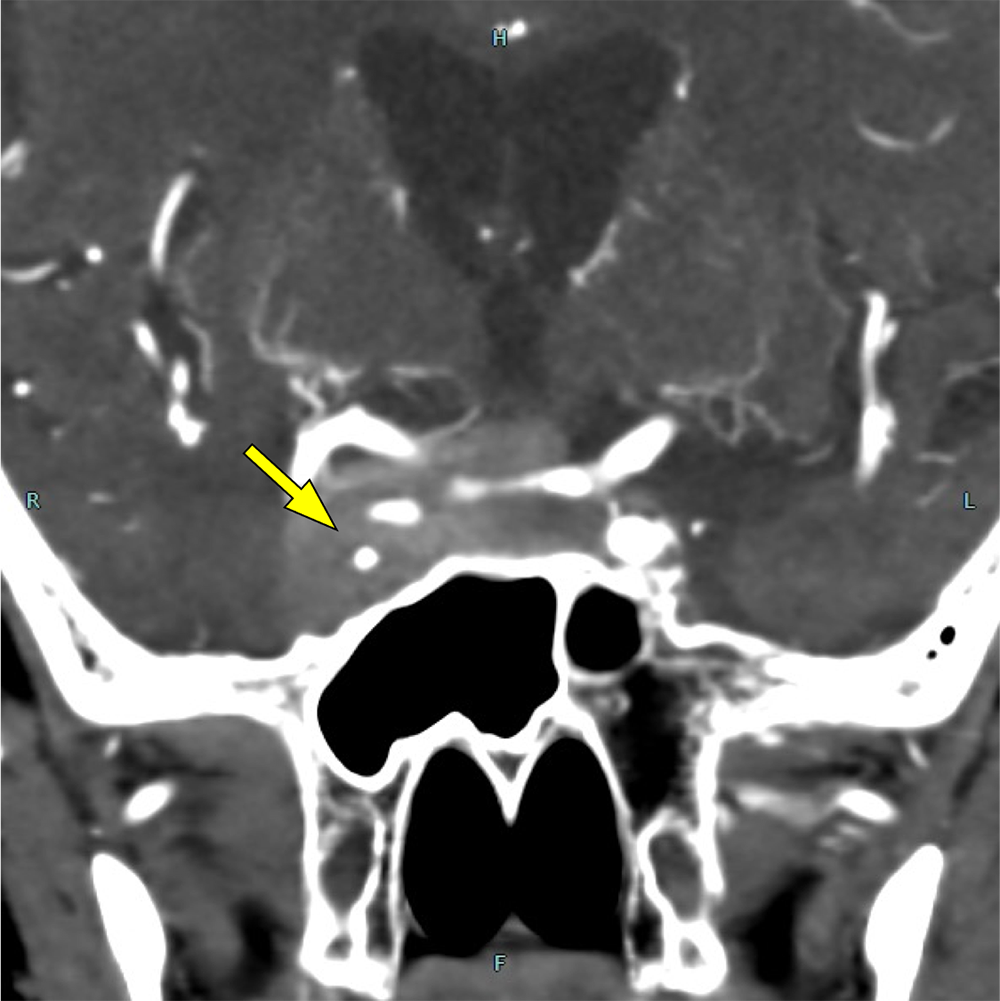

図3.造影CT(早期相)

右内頚動脈が腫瘤に取り囲まれ、対側より狭窄している。

図4.3D-CTA

右内頚動脈の海綿静脈洞部に狭窄を認める。